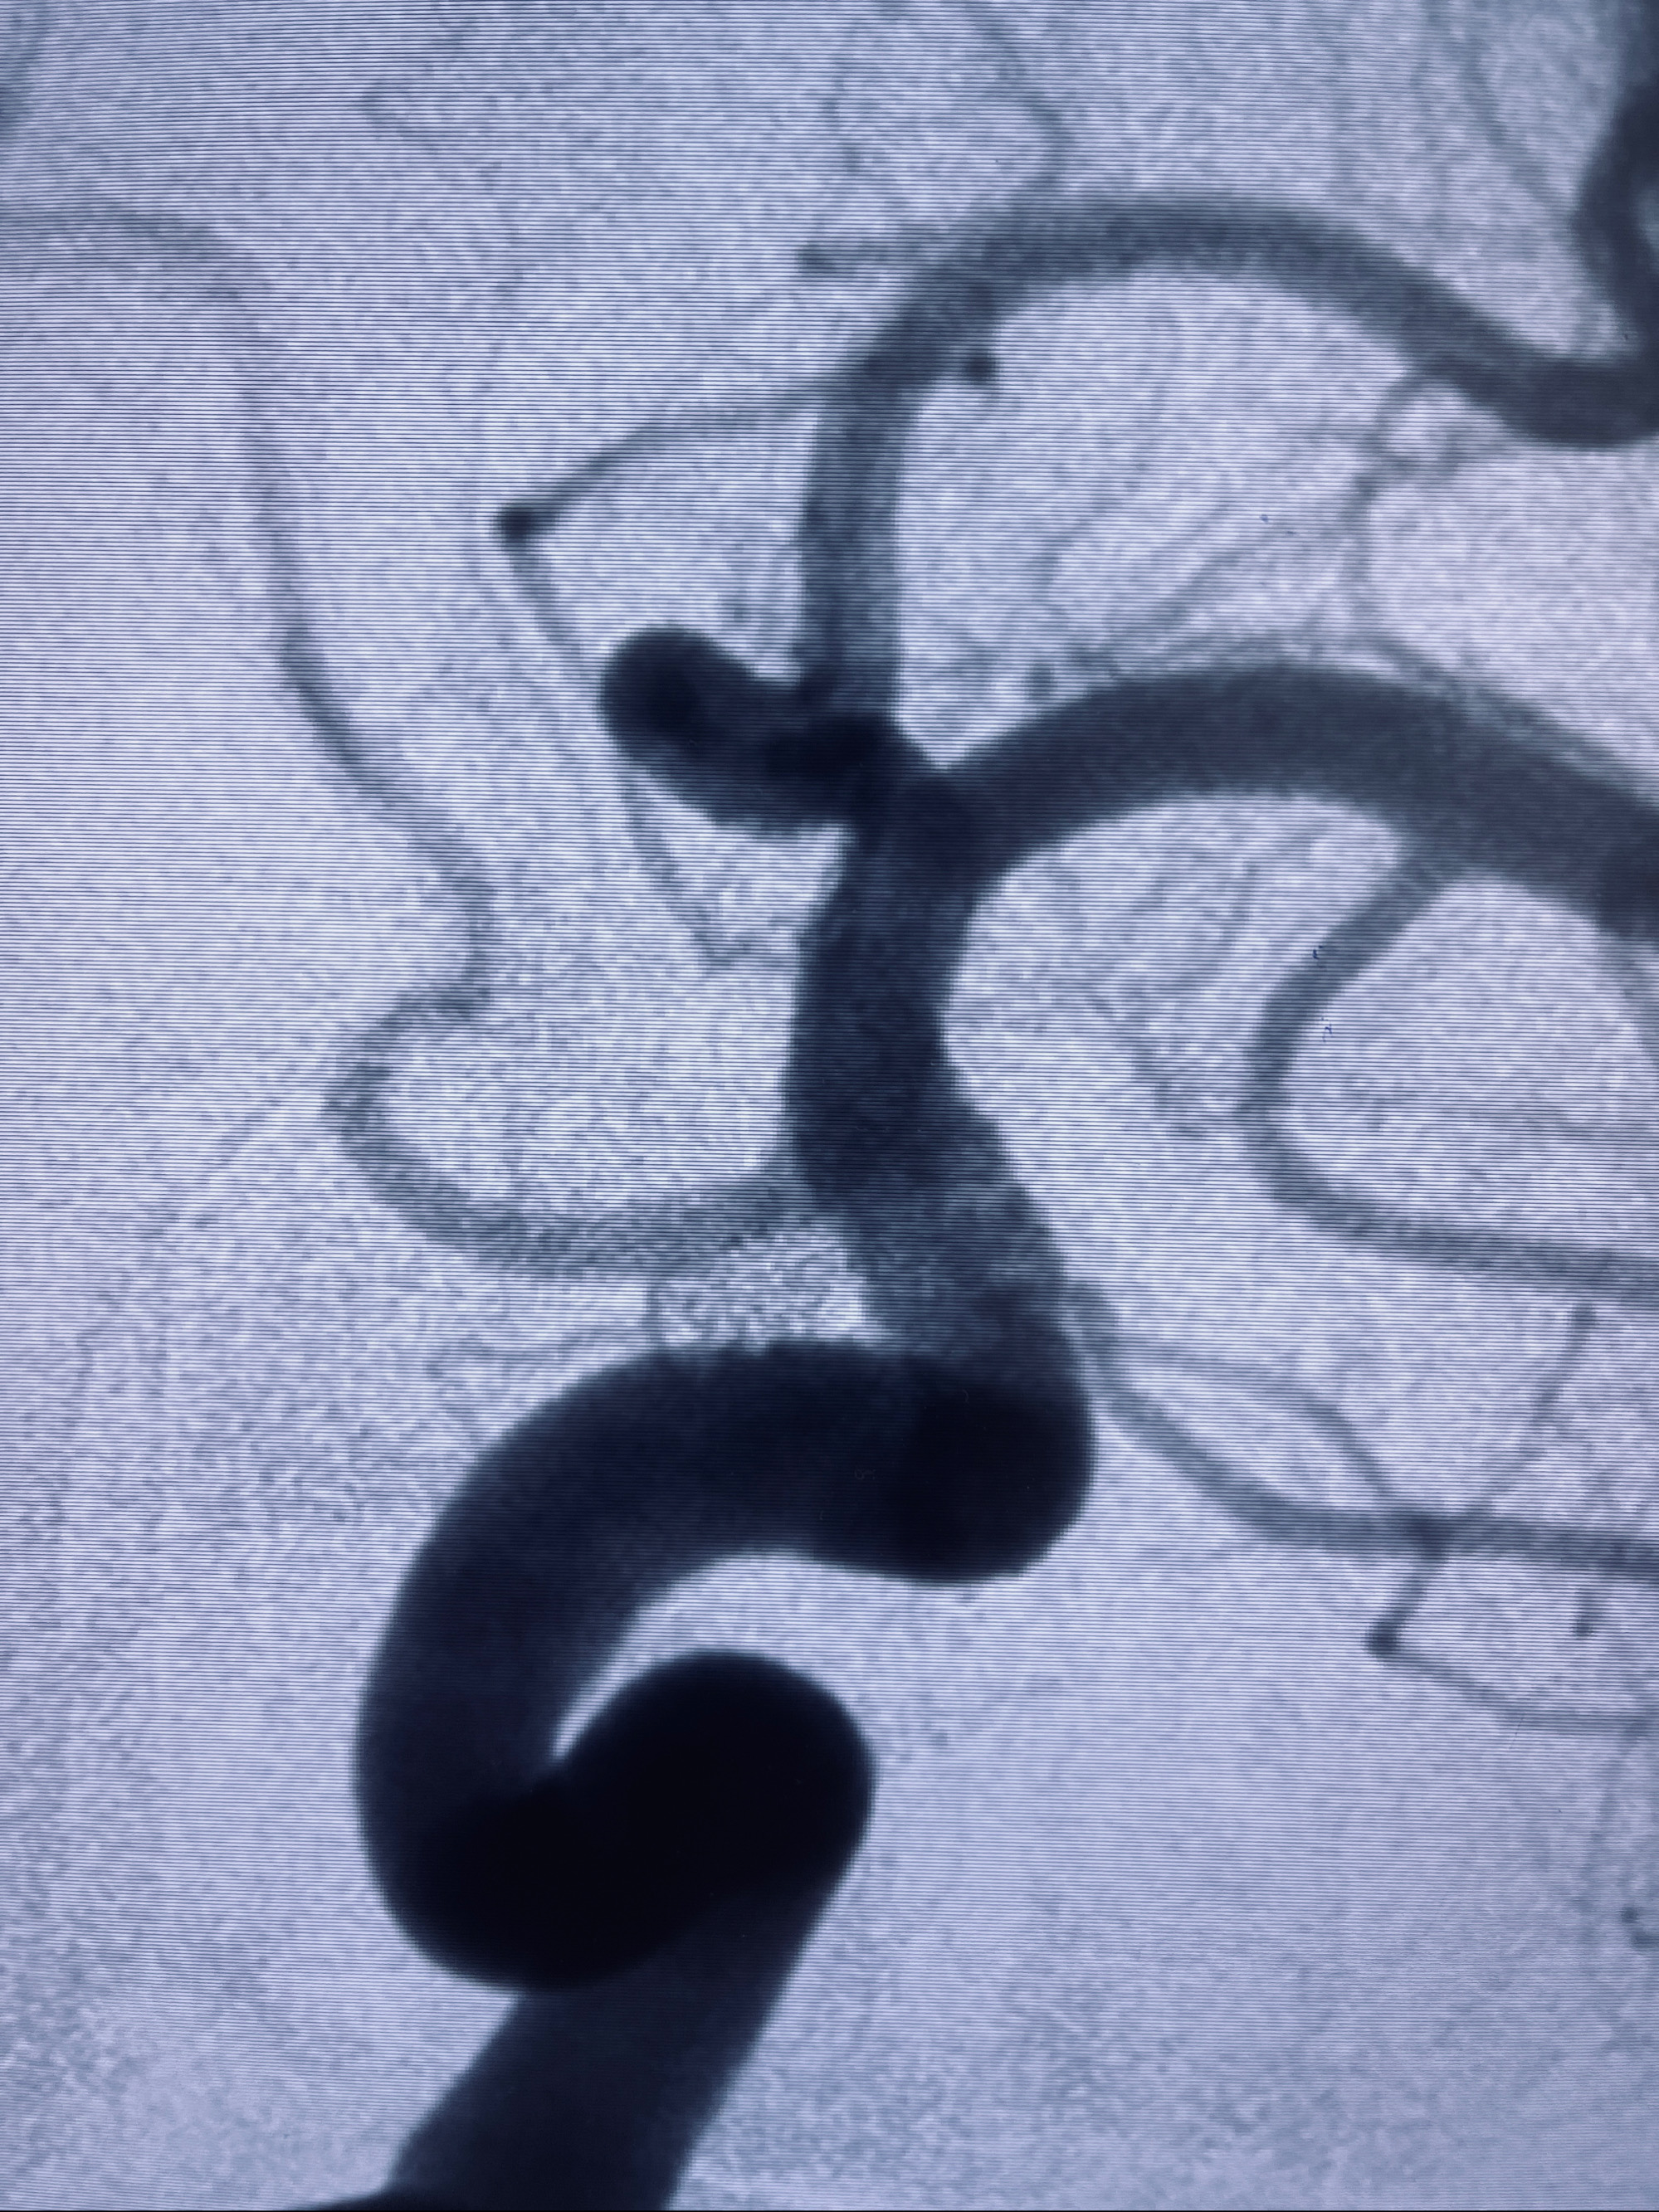

现病史:患者,女,因“左侧颈眼动脉瘤支架辅助栓塞术后1年余”入院。患者2021-5-24因“头晕”就诊于华山医院查头颅CTA、DSA诊断左侧颈眼动脉瘤,随后在全麻下行“左侧颈眼动脉瘤支架辅助栓塞术”,术顺,术后恢复可,予以阿司匹林、氯吡格雷抗血小板,阿托伐他汀钙片降脂稳定斑块。3月后华山医院复查脑血管造影动脉瘤未见明显复发或残留,停用降脂药物。目前患者无明显不适主诉,口服阿司匹林抗血小板治疗,为行脑血管造影收入我科。

2022-09-29复查DSA